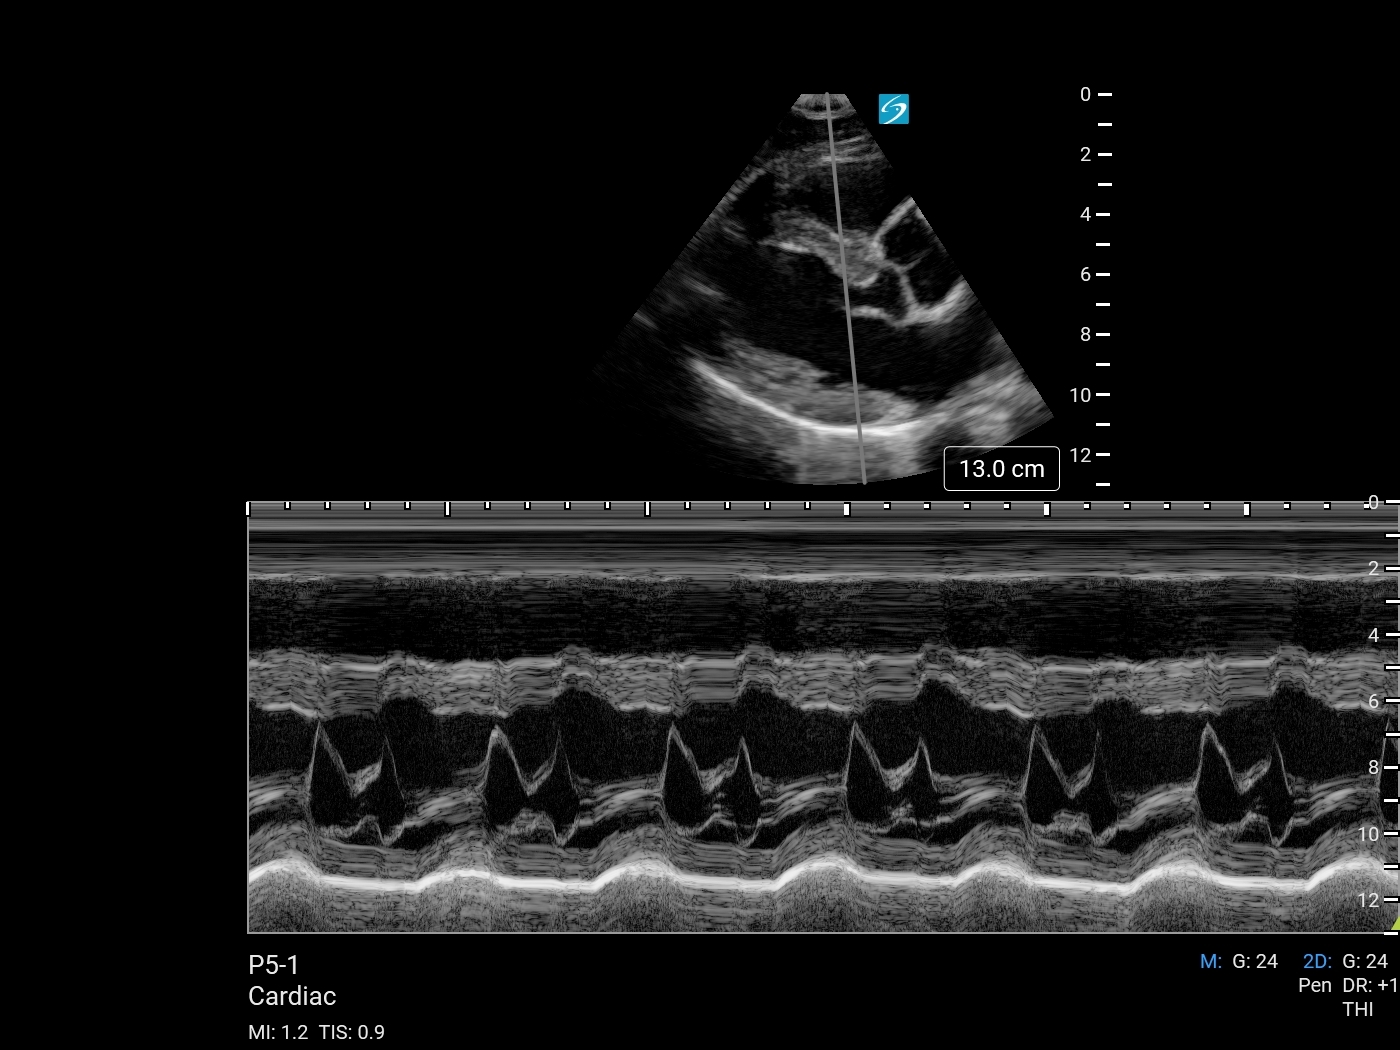

Heart M-Mode (Sonosite PX P5-1) Image